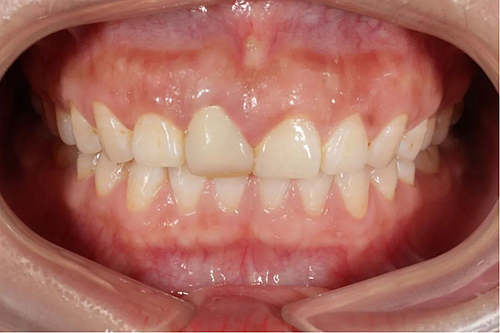

患者右上前牙因外傷冠修復(fù)體脫落來我院找口腔修復(fù)科金小婷醫(yī)師治療。經(jīng)檢查,患者剩余牙體組織少,經(jīng)溝通確認后,進行上前牙全瓷冠修復(fù)。

△最終修復(fù)